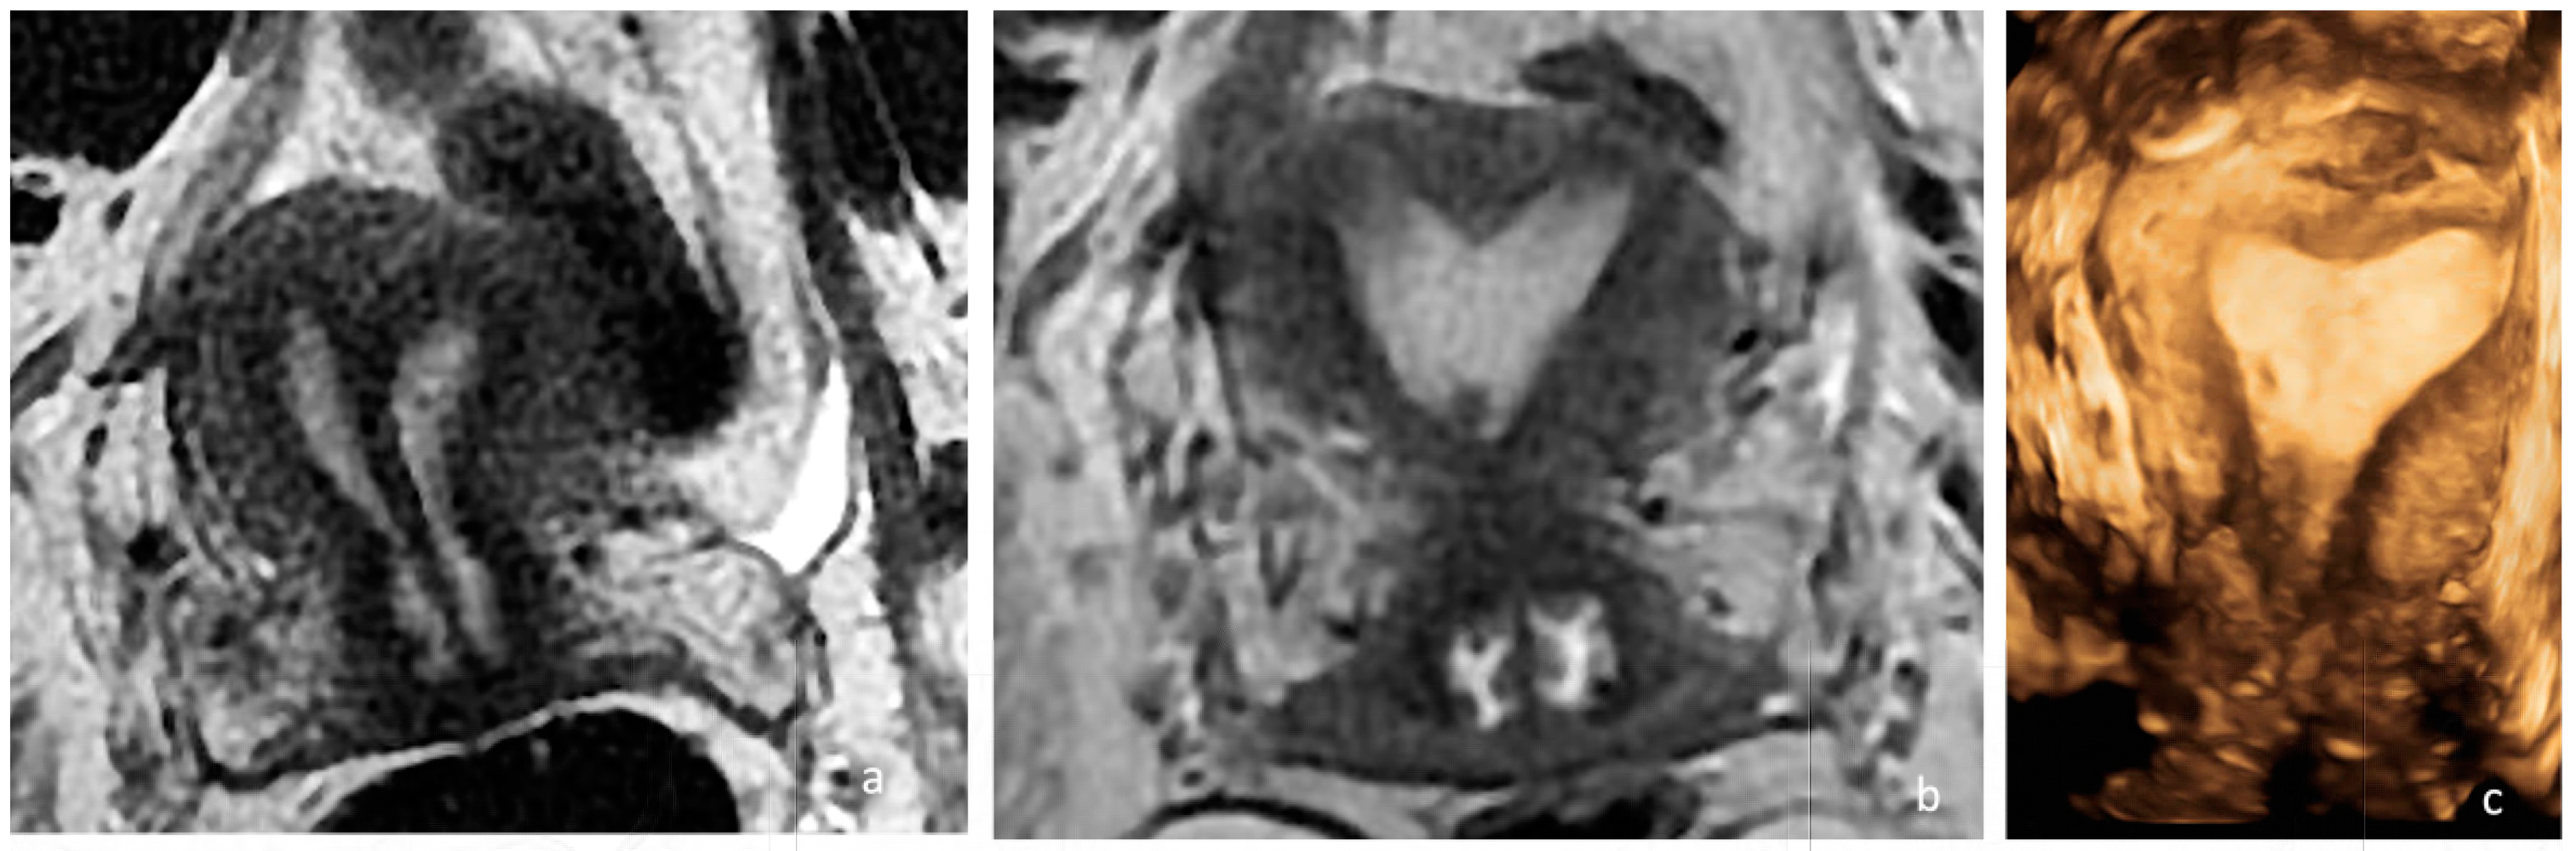

A pelvic examination revealed a longitudinal non-obstructing vaginal septum and distinct cervices on both sides. A transvaginal 3D ultrasound showed a complete uterine septum and a duplicated cervix. The ovaries and kidneys were normal. The pre- and postoperative pelvic MRIs are depicted in Figure 3. Like in the first case, hysteroscopic removal of the uterine septum up to the isthmic level, sparing the two cervices, and resection of the longitudinal vaginal septum were performed. A single uterine cavity was obtained (Figure 2b). The patient was discharged on the same day with a two-month estrogen pill regimen to prevent the occurrence of uterine synechia.

Figure 3. Preoperative and postoperative examination of case 2. (a) The preoperative MRI T2, WI, confirmed the presence of a Müllerian anomaly and identified it as a complete septate uterus, duplicated cervix, and longitudinal vaginal septum (Class U2bC2V1 of the ESHRE/ESGE classification). A complete septum with a thickness of 3 mm and a length of approximately 6 cm (measured from the intercolonial line) and 7.5 cm (measured from the level of the external contour of the uterus) was identified. (b) The postoperative MRI at 2 months confirmed the partial persistence of the septum in the supracervical region with the persistence of a slight indentation at the fundal level appearance of an arched uterus. (c) Three-dimensional ultrasonography performed 5 months postoperatively in which a normal uterine cavity was observed.

The postoperative MRI at 2 months is depicted in Figure 2b.

The control ultrasound examination performed 5 months after surgery revealed a relatively normal single uterine cavity, and the patient was scheduled to return in another two months for hysterosalpingography (Figure 2c).